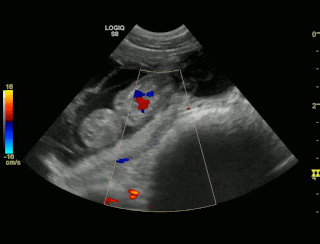

| 04.06.2018 |

Tessa und Uaine sind schwanger! Die Ultraschallbilder beweisen es! Hier die Bilder!!! |

| Hier die Ultraschallbilder von Uaine von Waltenweiler!!! |